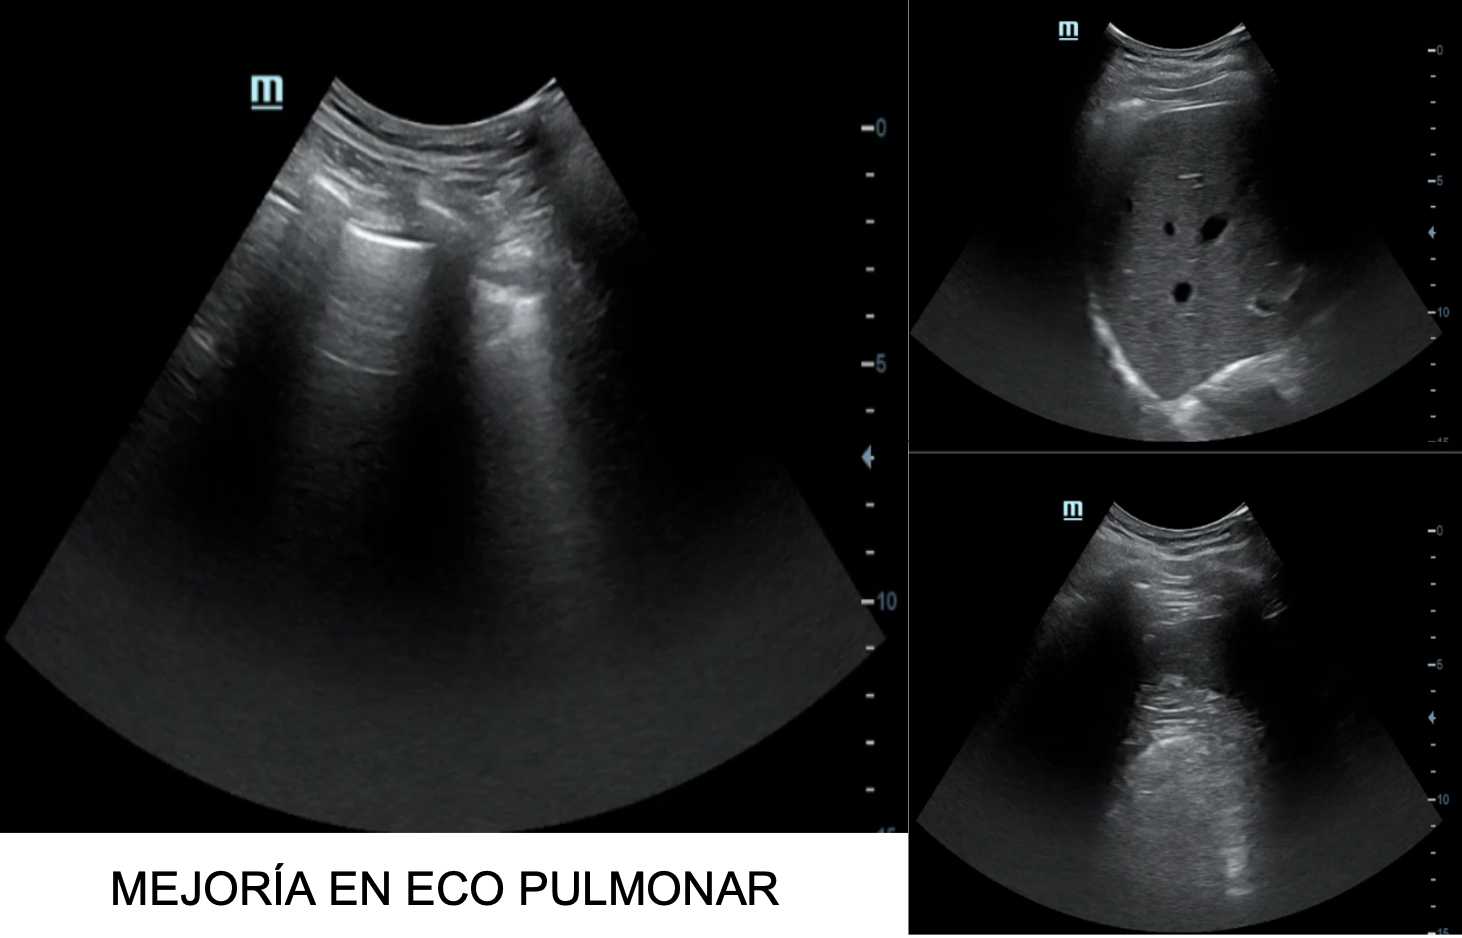

Descripción de los hallazgos ecográficos y las imágenes más relevantes para la resolución del caso

A la exploración ecográfica pulmonar se objetivan líneas B en ambos campos anteriores y superiores, así como derrame pleural bilateral, orientando la causa de la disnea hacia la insuficiencia cardíaca.

A posteriori en consulta se realiza ecografía de control donde se observa la desaparición de líneas B y resolución del derrame pleural bilateral.